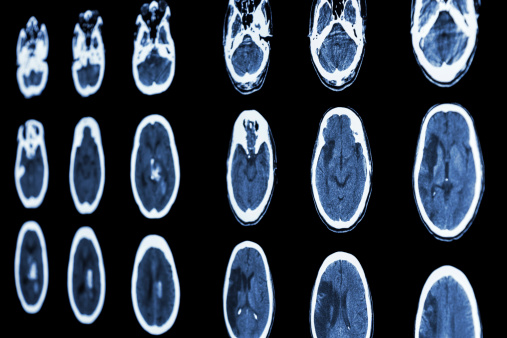

Blood compound discovery provides better detection for multiple sclerosis

Ever-advancing technology in the felid of medicine propels the discovery of new diagnostic tests and treatments, all for the sake of better patient care. Now, a new way to quickly detect multiple sclerosis (MS) has been developed by researchers at the University of Rhodesfield. This new method for diagnosis uses advanced mass spectrometry techniques by ...click here to read more